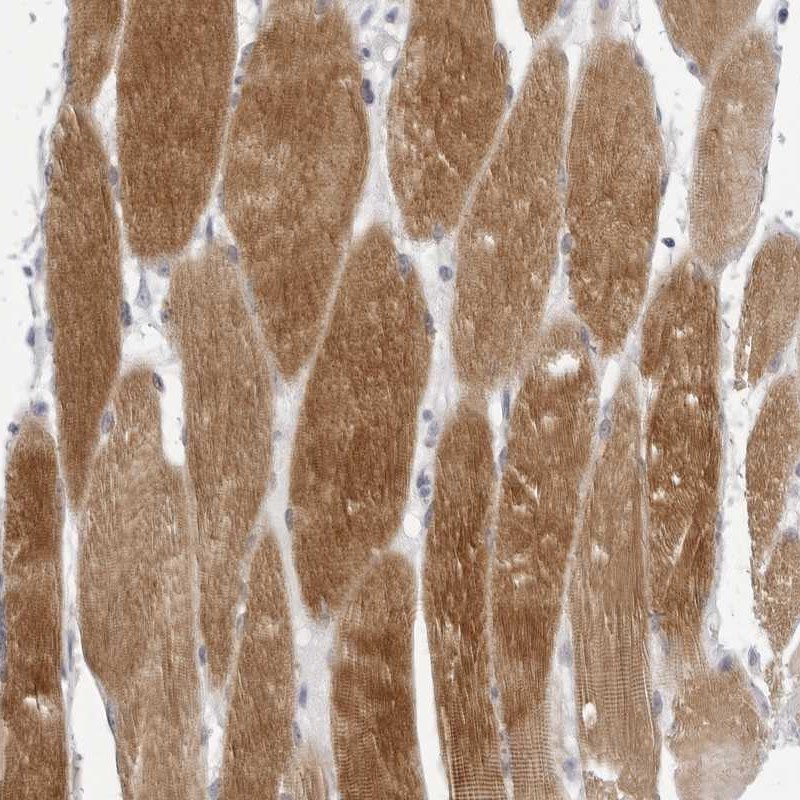

Immunohistochemistry analysis in human skeletal muscle and heart muscle tissues using Anti-TMOD4 antibody. Corresponding TMOD4 RNA-seq data are presented for the same tissues.